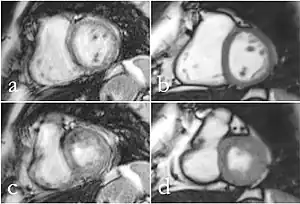

Although applications of real-time MRI cover a broad spectrum ranging from non-medical studies of turbulent flow[26] to the noninvasive monitoring of interventional (surgical) procedures, the most important application making use of the new capabilities is cardiovascular imaging.[1] Previous cardiac MR (CMR) used cine techniques to capture the periodic motion of the heart. However, this is not feasible for patients with arrhythmia, where the cardiac cycle is unpredictable.[27] With the new method it is possible to obtain movies of the beating heart in real time with up to 50 frames per second during free breathing and without the need for a synchronization to the electrocardiogram.[28] A study performed by Laubrock et. al[27] demonstrated that RT-MRI produced higher quality images with a higher SNR than cine CMR with a bSSFP sequence and radial k-space sampling. RT-MRI also removes the need for breath-holding while imaging, leading to a more comfortable experience for the patient as well.[27]